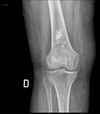

83

80 year old female with pain and swelling in the right knee. What is on your list of differential diagnoses in order from most to least common?

Stippled calcification = ICE 1. Chondrosarcoma 2. Infarct (Serpiginous) 3. Enchondroma

84

Give a list of differentials in order from most to least likely.

1. Chondrosarcoma (large calcified soft tissue mass) 2. Enchondroma 3. Infarct

80 year old female with pain and swelling in the right knee. Stippled calcification and history of Alcoholism. What is on your list of differential diagnoses in order from most to least common?

Stippled calcification = ICE 1. Chondrosarcoma 2. Infarct (plastic rags risk factor) 3. Enchondroma

87

39 year old female with pain and swelling in the right knee. Stippled calcification and known Gaucher disease. Also history of pregnancy. What is on your list of differential diagnoses in order from most to least common?

Stippled calcification = ICE 1. Infarct (plastic rags risk factor) 2. Enchondroma 3. Chondrosarcoma

88

39 year old female with pain and swelling in the right knee. Stippled calcification with Serpiginous contour. What is on your list of differential diagnoses in order from most to least common?

Stippled calcification = ICE 1. Infarct (Serpiginous contour) 2. Enchondroma 3. Chondrosarcoma